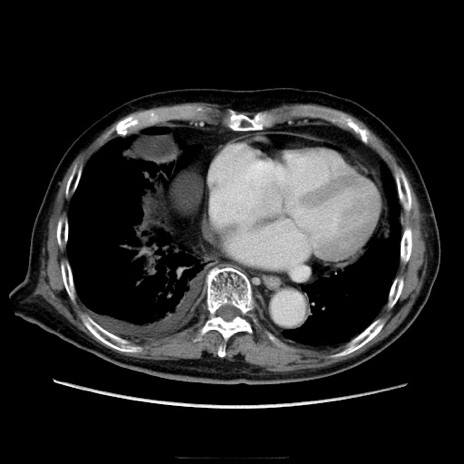

症例21(横断像)

【症例】70歳代男性

【主訴】腹痛

【現病歴】肝硬変・肝細胞癌にてかかりつけの方。約9時間前に食後より腹痛出現。症状が徐々に増悪し、嘔吐出現したため来院。

【既往歴】肝硬変、肝細胞癌(RFA、TACE後)

【身体所見】意識清明、表情苦悶様、BT 36℃、BP 129/78mmHg、P 88bpm、SpO2 97%(RA)、右上腹部から心窩部にかけて圧痛あり、反跳痛なし、筋性防御あり。

【データ】WBC 5800、CRP 0.16